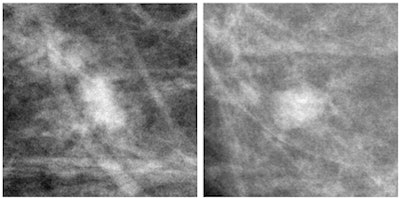

Masses

The pigeons found identifying masses on mammography to be a much harder task, and the training period was longer (almost 12 weeks instead of two weeks). Average accuracy scores during the testing period were 74% for familiar images and 44% for new ones.

"Correctly identifying these challenging target masses is difficult even for trained radiologists; and in fact, it proved to lie at the limits of the pigeons' capabilities," the group wrote.